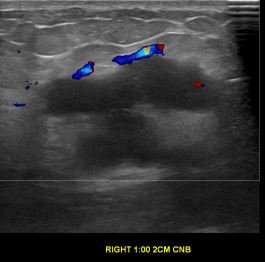

상기환자는 우측 유방 만져지는 멍우리로 내원하신 50대중반 여성분으로 의심스러운 우측혹 조직검사 시행해 유방암으로 진단되었습니다